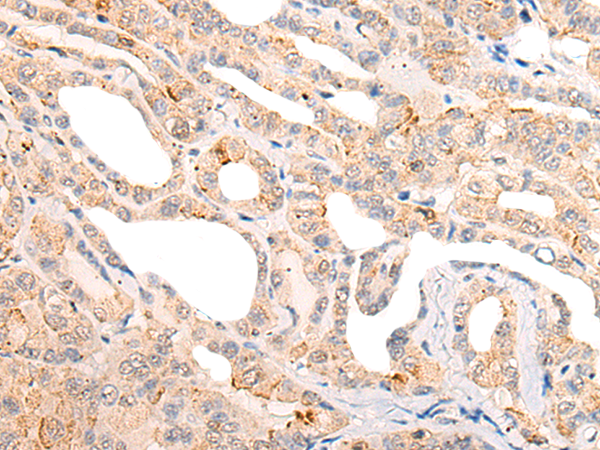

分类: 科研抗体货号: P02533别名:应用: WB,IHC反应种属: Human, Mouse, Rat